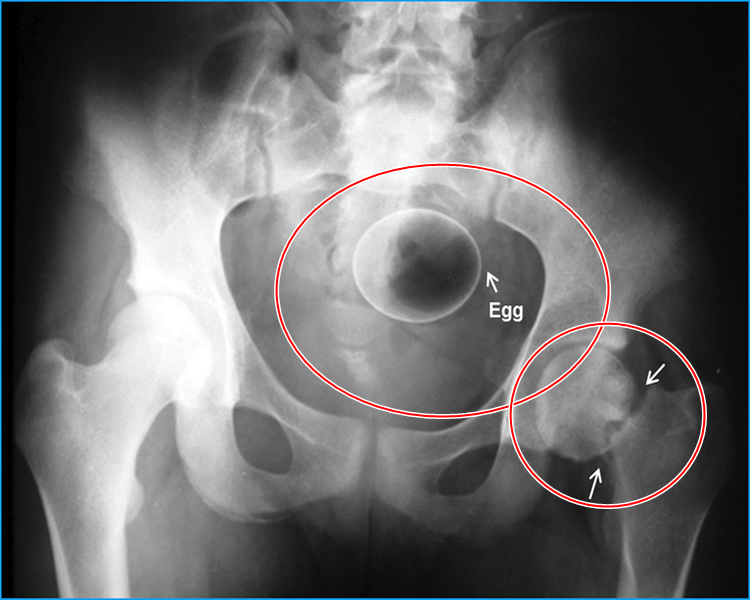

Dois ovos de galinha introduzidos na região íntima